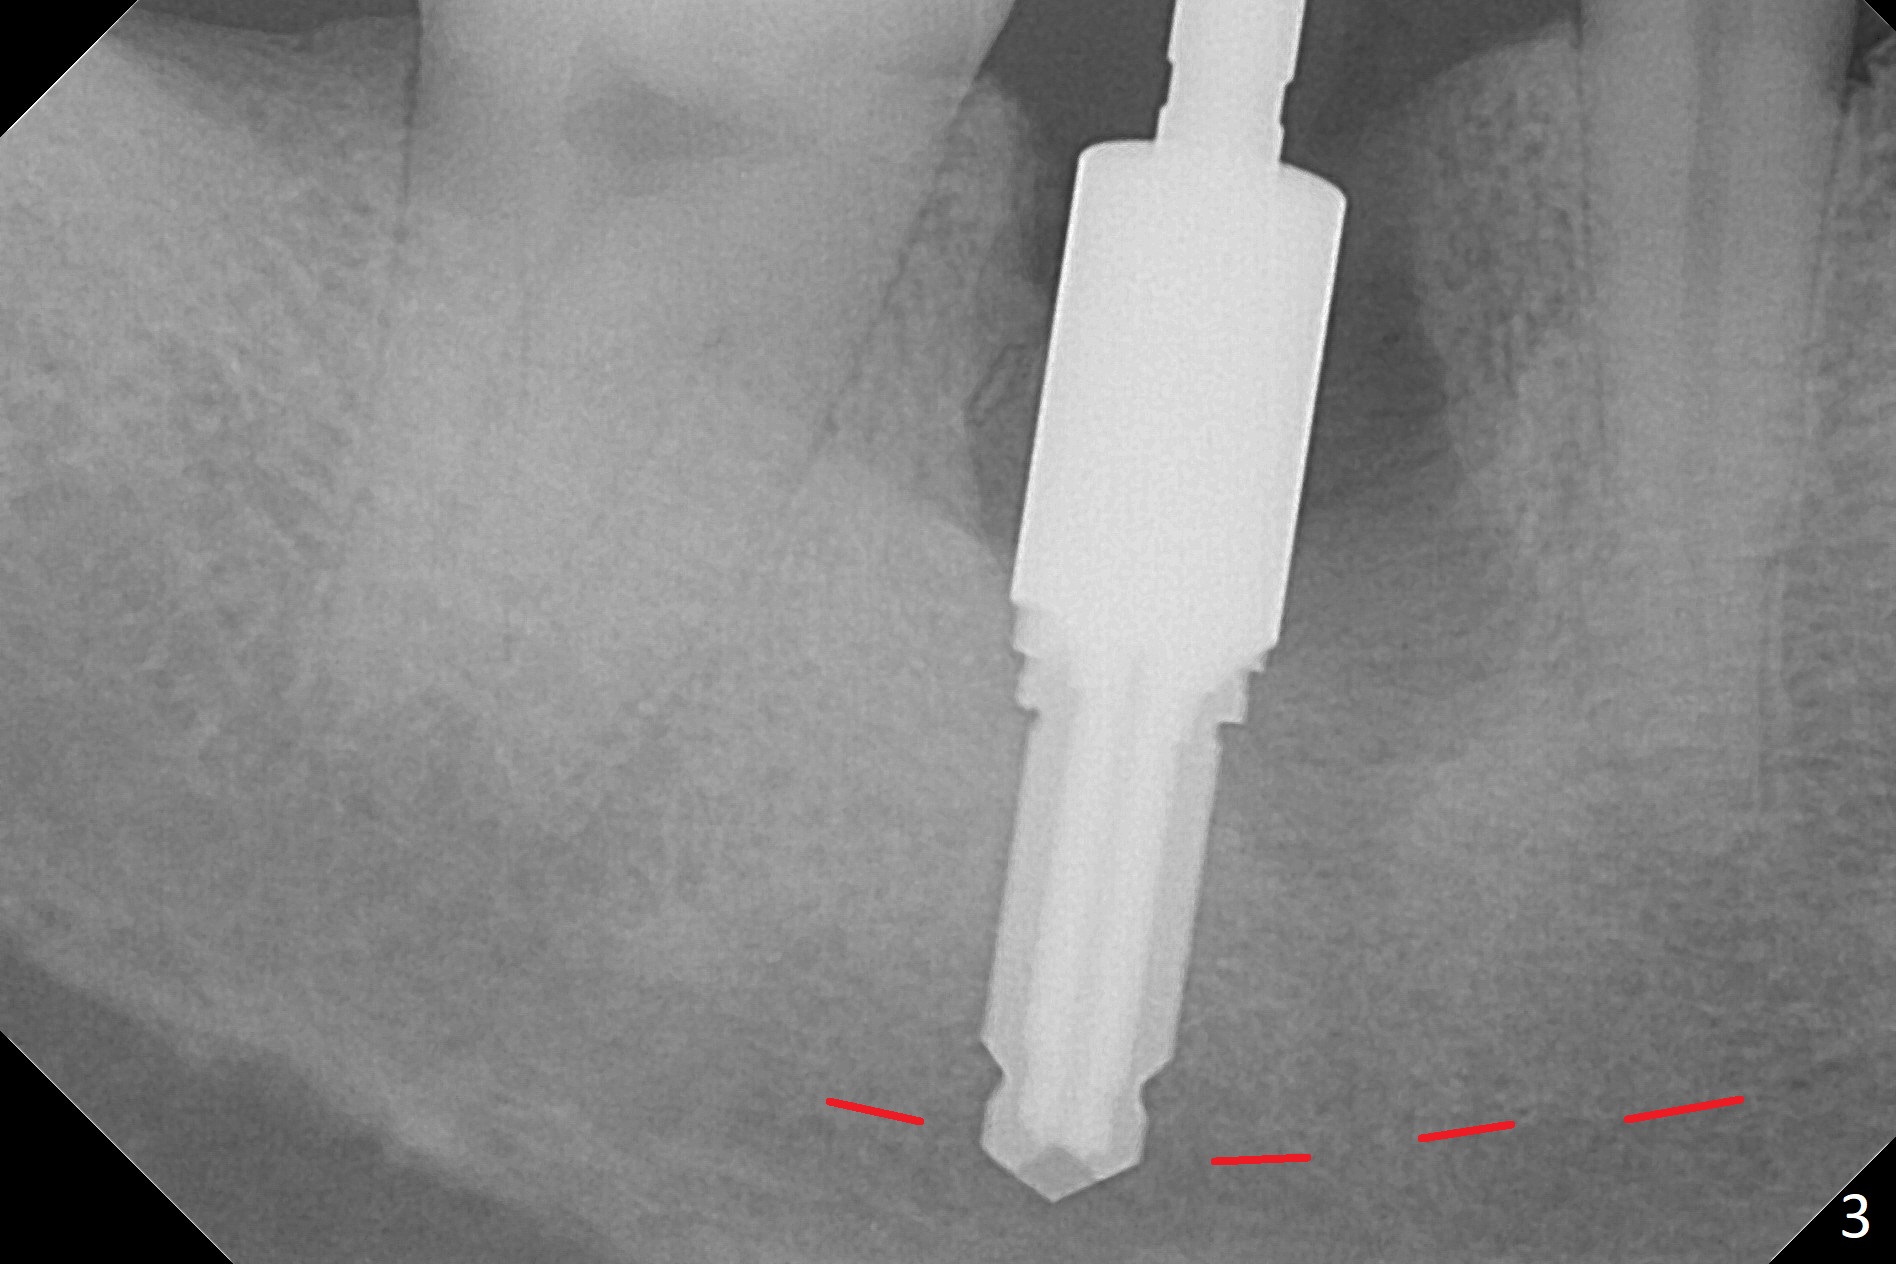

After the tooth #30 is extracted, the socket is 18 mm deep and the lingual plate is 4 mm tall. With hemorrhage, visibility of the socket, especially the bottom, is poor. The septum is almost completely defective. Following removal of the most buccal portion of the septum, osteotomy is initiated as buccal as possible, but it is mesial (Fig.1). In spite of effort to move the osteotomy distal, the osteotomy remains mesial and superficial (Fig.2 with 5 mm tap drill). Pain control is poor with infiltration. It appears that the smaller osteotomy (Fig.2 yellow line) may have extended close to the superior border of the Inferior Alveolar Canal (red line). It appears that there is 8.5 mm bone distal with ~ 2 mm clearance. After mandibular block, a new osteotomy is made distal; when a 3.8 mm drill is being used, there is hemorrhage from the osteotomy with apparent violation of the Canal integrity (Fig.3,4). But hemostasis is achieved with gauze pressure. A 5x13 mm implant is placed superficially (Fig.5) with a trace of the previous osteotomy (yellow line) and deep space created by the mesial osteotomy (*). Apparently the pathological and iatrogenic defects are filled with allograft (Fig.6 *). Guided surgery could have avoided the mesial osteotomy.